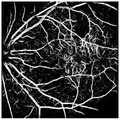

Fig. 6 shows a color retinal fundus image and an SLO retinal fundus image.

FIG. 7 is a graph of the results of training using an expert labeled color retinal fundus database, learning without adding domain adaptation, and then testing on an SLO retinal fundus image;

FIG. 8 is a diagram showing the results of manually labeling an SLO retinal fundus image and then testing on the SLO retinal fundus image;

FIG. 9 is a graph of the results of a training test using the method described in embodiments of the invention.

The color retinal fundus image (left) and SLO retinal fundus image (right) are shown in fig. 6. The blood vessel segmentation effect graphs are shown in fig. 7, fig. 8 and fig. 9, wherein fig. 7 is the result of training by using a public color retina fundus database labeled by experts, no domain-added adaptive learning is performed, and then testing is performed on an SLO retina fundus image; fig. 8 is a result of manually labeling an SLO retinal fundus image and then testing on the SLO retinal fundus image; FIG. 9 is the result of a training test using the method provided by the present invention, i.e., training using a public database of expert labeled color retinal fundus, joining in domain adaptive learning, and then testing on an SLO retinal fundus image. It can be seen that the results of fig. 7 are cluttered in background, with many more results than blood vessels, which also demonstrates that the feature distribution is different between different modalities; the results in fig. 8 present a sense of distortion and the small vessels appear to be relatively bulky, requiring considerable time and effort to manually label the images, and presenting labeled results that are subject to error; the results in fig. 9 not only provide a clean background, but also provide a good segmentation of retinal vessels with a reasonable degree of vessel thickness.